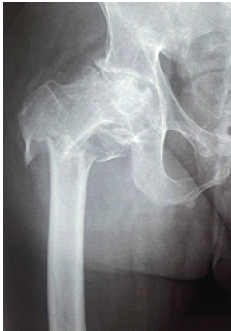

Management of Subtrochanteric Femur Fracture with Pre-existing Grade IV Psoriatic Hip Arthritis Using Primary Total Hip Arthroplasty with a Long Distal-Loading Stem: A Case Report

K Praveen , Muthukannan Hari Sivanandan , I Shebin Christin , S Gokul , M Sriram

………………………………p.44-49